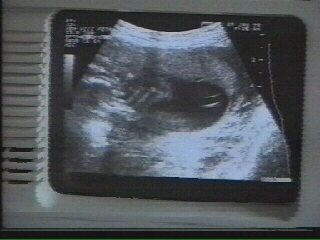

20:15 Pictures from an ultrasonogram

20:29 Ultrasound scanning of a pregnant woman